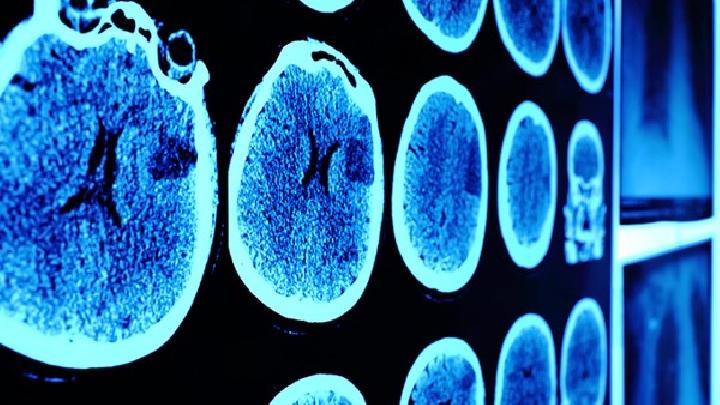

1.与其他脑血管疾病 不同,脑出血和脑梗死的治疗非常重要。轻度脑出血和脑梗死仍难以识别,此时应进行脑出血CT扫描。对有明显意识障碍者应与颅内大动脉(如大脑中动脉主干)闭塞相鉴别。在患者情况允许或尚无条件进行CT扫描时,为了区分出血性或缺血性脑血管疾病,表2是大多数教科书中常用的鉴别表。

2.脑肿瘤的鉴别 脑肿瘤一般表现为颅内压升高和神经系统定位征逐渐加重,根据病史、体征,特别是脑结合CT扫描并不难做出诊断。然而,少数病例,特别是老年病例的早期症状并不典型,类似于缺血性脑血管疾病的形式,没有明显的颅内压增加症状,大脑CT症状与脑梗死相似,容易误诊。部分脑肿瘤患者由于肿瘤出血,可使病情突然恶化,临床表现与脑出血相似,因此在临床上应高度重视。一般脑肿瘤患者经过临床积极治疗,颅压降低后症状可短暂改善,但总体趋势是病情加重。因此,对于颅内高密度病变,除脑出血外,还应考虑脑肿瘤的可能性。必要时,可进行强化扫描。

脑瘤引起的脑血管疾病,即脑瘤卒中,以及脑血管疾病的鉴别,以下几点可供参考:①脑瘤性卒中一般不伴有高血压,脑血管疾病多有高血压史。②脑瘤性卒中多由转移瘤引起,表现为原发病变,而脑血管疾病则无相关症状。③脑瘤性卒中脱水及对症治疗后,症状可暂时改善,但症状迅速反复,仍会加重。脑血管疾病治疗改善后,一般不会重复。④脑瘤性卒中偏瘫较轻,常伴有癫痫发作,而脑血管疾病偏瘫较重,癫痫发病率较低或无。⑤脑瘤性卒中眼底检查视盘水肿严重,常进行性加重;脑血管疾病视盘往往无水肿或水肿较轻,大部分治疗后迅速消失。⑥脑瘤性卒中多有头痛、呕吐等颅内压升高的病史,并逐渐加重,而脑血管疾病多为急性发病,既往无颅内压升高的病史。⑦一般来说,脑瘤性卒中发病较慢,症状多为持续性和进行性加重;脑血管疾病的发病相对较急。⑧脑CT以及大脑MRI可明确诊断检查。